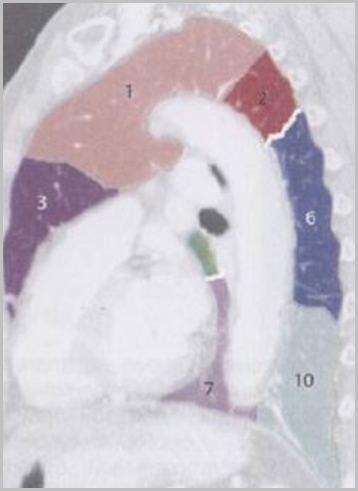

Анатомические изображения сегментов легких различных животных

Раздел: Другие животные